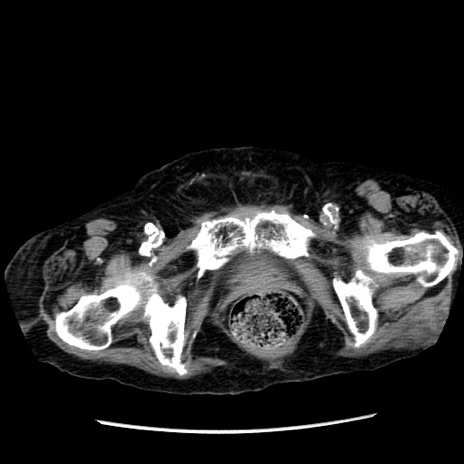

症例14(横断像)

【症例】 90歳代女性

【主訴】 腹痛・嘔吐

【現病歴】今朝から左側腹部痛を認めた。 経過観察していたが、嘔吐を認めたため来院。

【既往歴】 子宮癌術後

【身体所見】 意識清明、BP 127/54mmHg、P 98bpm Sp02 95%(RA)、BT 35.8°C、腹部平坦・軟腸ぜん動音聴取良好、右下腹部圧痛(+) 反跳痛なし

【データ】WBC 9800、CRP 0.46